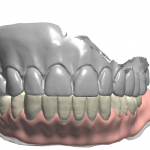

upper denture duplicated with shining 3d. only needed the occlusal and buccal surfaces as the case is for a lower overdenture over immediate extractions, on healed implants. went ahead and just duped the whole denture with the ios. very good results